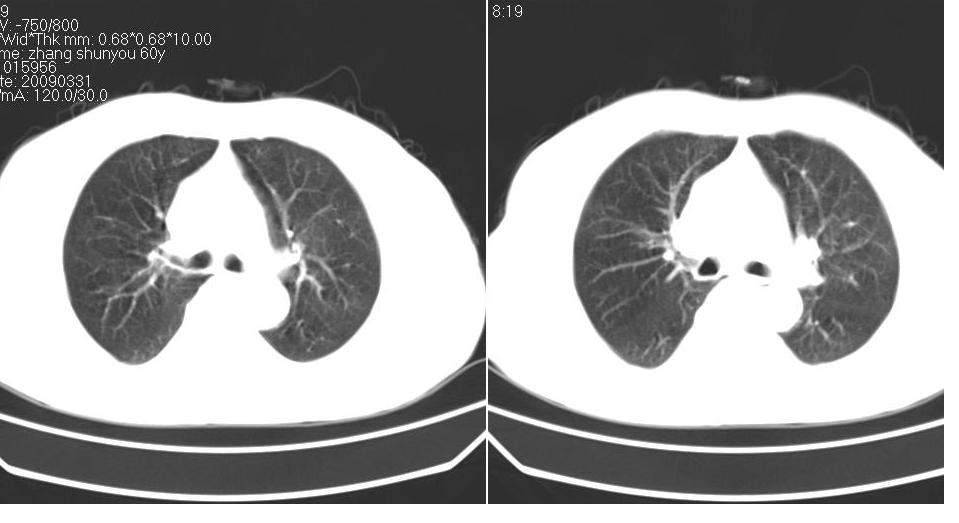

标题: CT19131:男 60岁,咳嗽,喀痰,胸闷,有吸烟史,胸部CT平扫 [打印本页]

男 60岁,咳嗽,喀痰,胸闷,有吸烟史,正常图片未上传,请谅解。

左肺肿块有分叶、有毛刺,符合周围型肺癌。

分叶状肿块,有毛刺,有晕,有粗纹理直通肺门,支持考虑周围型肺癌